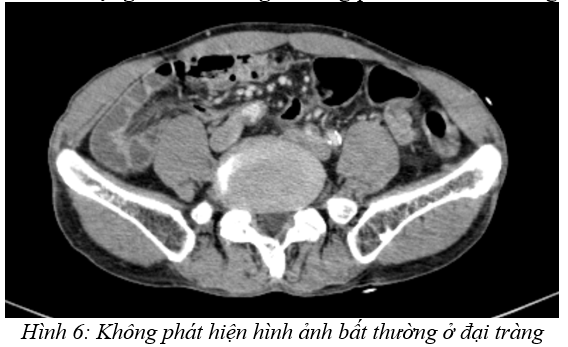

Cắt lớp vi tính lồng ngực: Không phát hiện bất thường.

Cắt lớp vi tính ổ bụng – tiểu khung: Không phát hiện bất thường.